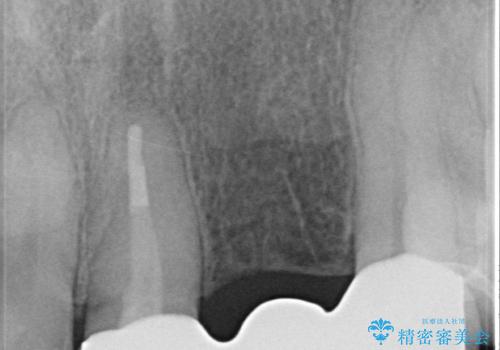

左上1、2番目の歯は仮歯の状態だったので外して状態を確認したところ、左上2は垂直的な歯根破折を認めたため抜歯となりました。左上1は再根管治療を行いました。

左上2抜歯後、骨および歯肉の回復を待ち、オールセラミッククラウンのブリッジによる欠損補綴を行いました。